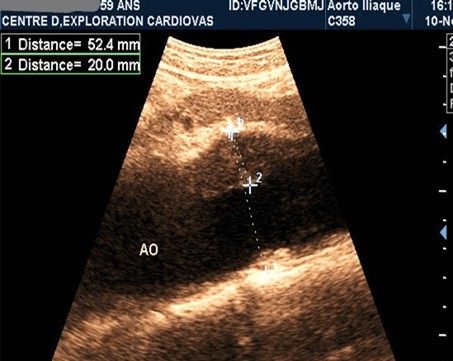

AAAs were fusiform in 23 patients (71.9%). The saccular aneurysm was present in 9 patients (28.1%). Figure 1 and (Figure 2).

Figure 1.Partially thrombosed 5.2cm fusiform suprarenal AAA with extension to the superior mesenteric artery in a 59-year-old subject (CEC 'Saint-Esprit' of the AMP-MCV).

Figure 2.Partially thrombosed 5.2cm fusiform suprarenal AAA with extension to the superior mesenteric artery in a 59-year-old subject (CEC 'Saint-Esprit' of the AMP-MCV).